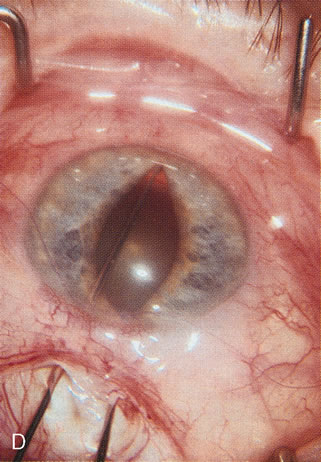

Cataract extraction by any technique performed in a patient with a pre-existing filter will have an effect on the previous filtering bleb.121–124 Bleb failure is more likely with ECCE compared with small-incision phacoemulsification.125 However, even patients undergoing topical anesthesia with clear corneal phacoemulsification and foldable IOL may experience bleb failure. One of three patients with a functioning filter and preoperative mean IOP of 12 mm Hg without antiglaucoma medications experiences bleb failure after lens extraction (Table 2). These patients require long-term drug therapy or bleb needling to control IOP. 126 Additional incisional glaucoma surgery may eventually be required in up to 10% of patients.127 Intraoperative iris manipulation may cause significant breakdown of the blood–aqueous barrier, resulting in inflammation that causes bleb failure. Even after uncomplicated clear corneal phacoemulsification, IOP may increase an average of 2 to 3 mm Hg due to bleb fibrosis.128 Approximately 20% of filtered patients require a long-term increase in glaucoma medications following uncomplicated clear corneal phacoemulsification with a foldable copolymer acrylic IOL129 (Fig. 3). In situations in which the bleb is not working at all, the eye will have a postoperative pressure spike that mimics that in the patient not having had a prior filtering procedure. In situations in which the bleb is marginal, the pressure spikes tend to be lower, and the final postoperative IOP tends to be around 50% higher than it was preoperatively. These patients require combined procedures in order to reestablish long-term filtration. In situations in which the bleb is very thin, polycystic, and associated with an IOP around 5 to 8 mm Hg on no antiglaucoma therapy; uncomplicated cataract extraction will have a minimal effect on the level of IOP. Patients with functioning glaucoma drainage implants usually have minimal long-term changes in IOP after uncomplicated cataract extraction.130

Fig. 3. Partial bleb failure following clear corneal phacoemulsification with foldable IOL. A. Preoperative bleb appearance prior to temporal lens extraction. Preoperative IOP was 12 mm Hg on no antiglaucoma medications. Time from 5-FU trabeculectomy surgery to lens extraction was one year. B. Bleb appearance 2 months after clear corneal cataract surgery with topical anesthesia. Following lens extraction, increased vascularity was noted along with decreased size of the filtering bleb. IOP increased to 20 mm Hg as early as 2 weeks after surgery, necessitating topical antiglaucoma therapy. C. High magnification view of bleb before lens extraction demonstrates diffuse pale bleb. D. High magnification view of bleb 2 months after surgery. There are vessels surrounding the nasal side of the bleb and the overall bleb size is smaller.